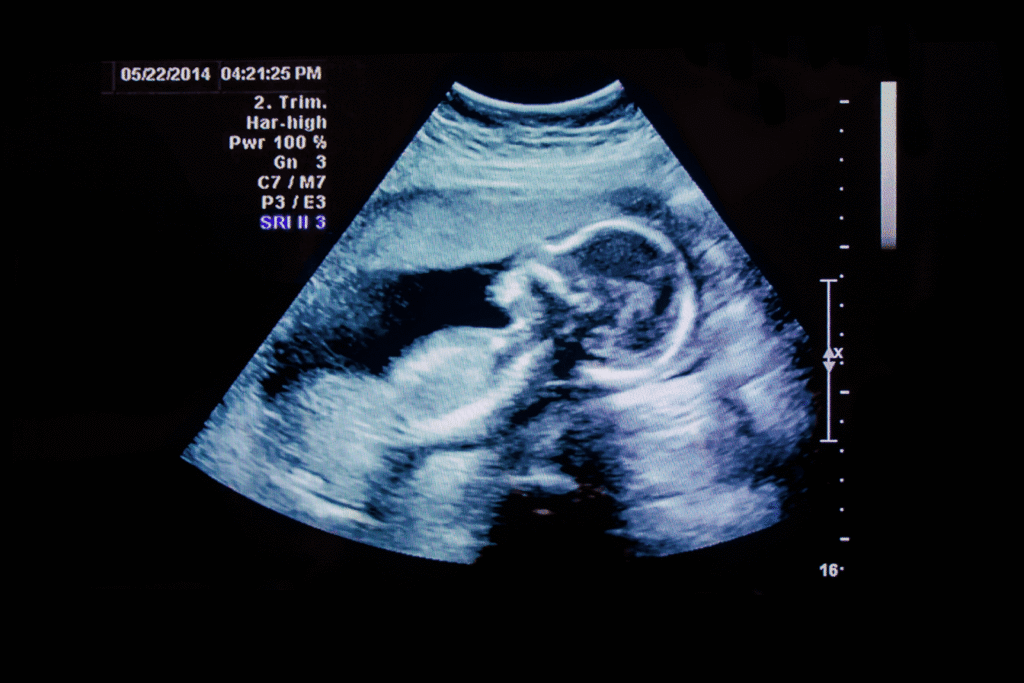

Fetal ultrasounds and related imaging studies generate large files that accumulate quickly. Managing these images on traditional local servers can strain storage capacity and slow down retrieval times. Cloud PACS offers scalable storage that grows with your practice, eliminating concerns about running out of space or investing in costly hardware upgrades. As imaging technology continues to advance, the resolution and quality of fetal images are improving, leading to even larger file sizes. This trend emphasizes the need for a robust storage solution that can accommodate not just current needs but also future demands as practices expand their imaging capabilities.

OmniPACS offers a cloud-native platform designed for medical imaging workflows, including fetal ultrasound. Its diagnostic viewer is FDA-cleared, ensuring clinicians can rely on it for accurate image interpretation. The platform supports both diagnostic and non-diagnostic viewing, making it versatile for various clinical scenarios.